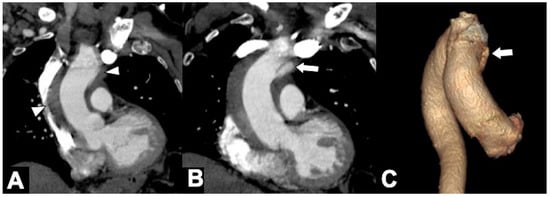

| True Lumen | False Lumen |

|---|---|

| Surrounded by calcifications (if present) | Delayed enhancement, slower flow |

| Hyperdense in early arterial phase | Hyperdense in the venous phase |

| Smaller than a false lumen | Larger than a true lumen |

| Continuity with an undissected aorta | Not connected to the unaffected aorta |

| Intima displaced inwards | Beak-sign, Cobwebs sign |

| Calcification along the intimal flap | Circular configuration |

| Outer wall calcification/s | Lack of outer wall calcification/s |

| Usually origin of CT, SMA, and RRA 1 | Usually origin of LRA 2 |

| Inner lumen in aortic arch | Partial thrombus formation |

| Wrapped around the false lumen | Wrapped around the true lumen |